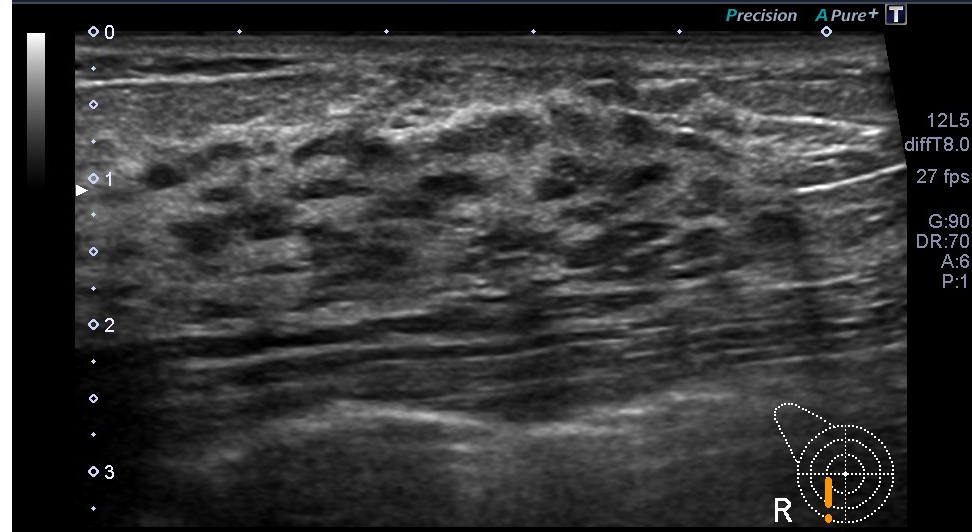

超音波(エコー) 診断画像

- 乳腺症

- 乳がん